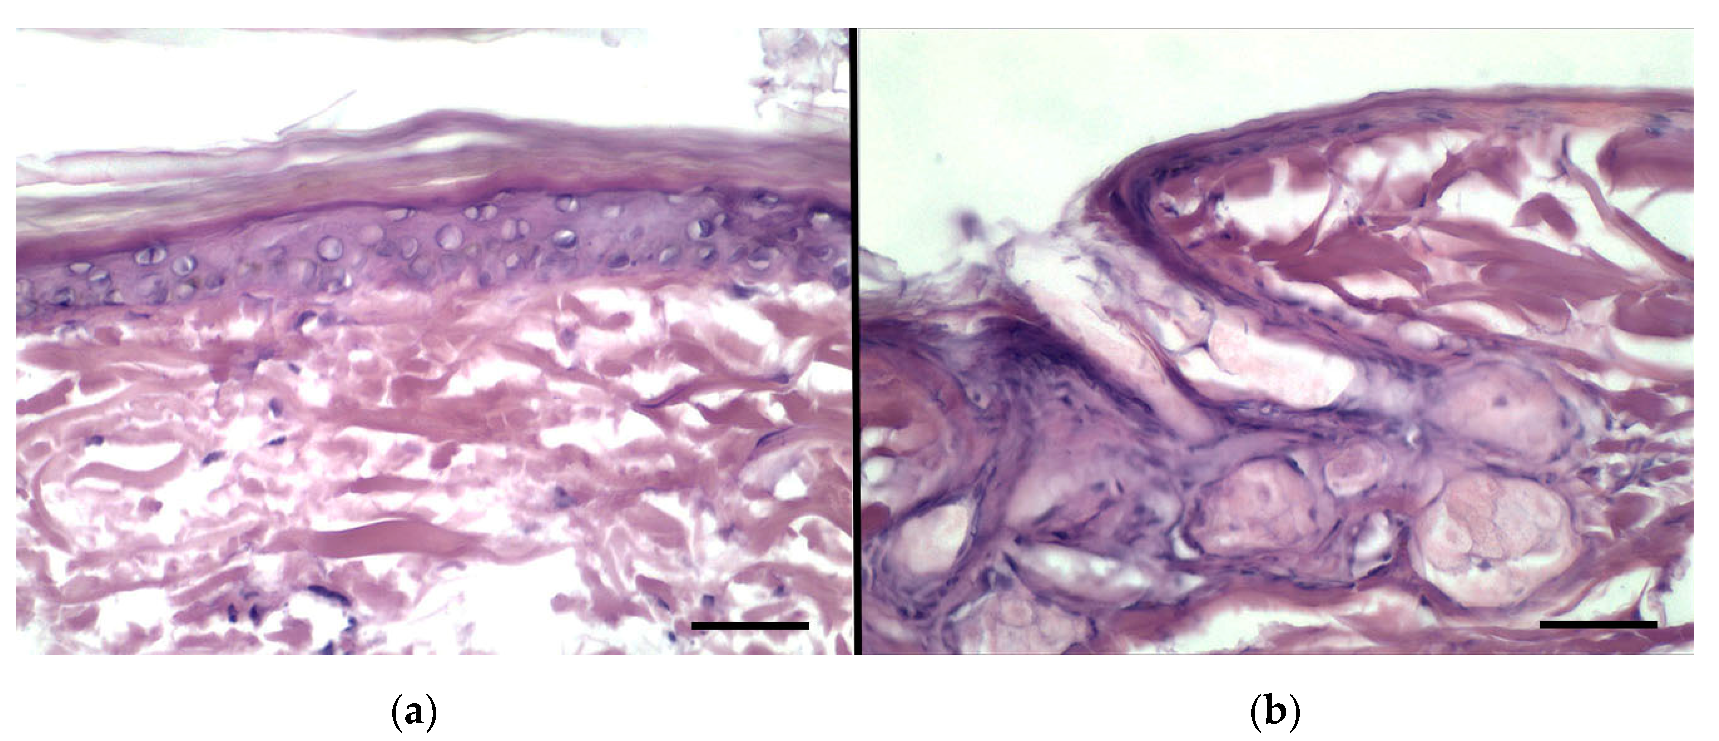

3.8. Histological Evaluation of Rabbit Ear Skin and Human Abdominal Skin

The rabbit ear skin was reported to possess a similar thickness of the stratum corneum compared with pig ear skin, although the underneath epidermal layers have a slightly different structure, for this reason, it has been proposed as a reliable model for in vitro transdermal tests [35]. In the present study, the rabbit ear skin tissue was histologically evaluated as a substitute for human abdominal skin. Figure 7 shows representative histological sections of rabbit ear skin (Figure 7a) and human abdominal skin (Figure 7b). In both pictures, the various layers of the epidermis and the dermis can be easily identified. To note that, in some areas, the stratum corneum appears detached from the underlying layers, probably due to freezing and sectioning artifacts. The histological structure was very similar in both tissues, with the exception of sweat glands, which were lacking in the rabbit skin. The results suggested that the rabbit ear skin is a suitable model to study both lipophilic and hydrophilic permeants.

Figure 7.

Light microscopic images of (a) rabbit ear skin and (b) human abdominal skin. In both specimens, the epidermal epithelia show a thin stratum corneum. Bars = 50 μm.